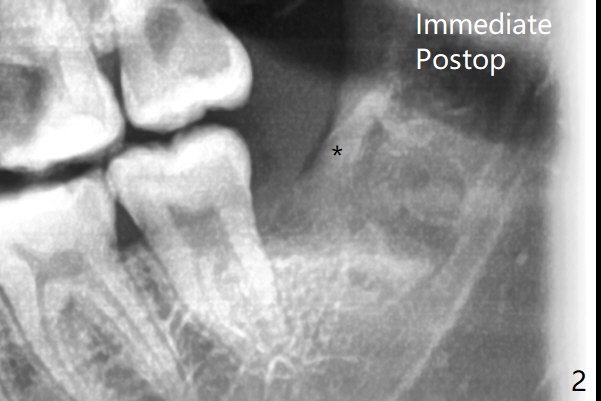

20岁女由于右下智齿疼痛就诊,诊断后,要求先拔除两个下颌智齿。外斜嵴好像跨越牙槽窝远中(图一:*),拔除似乎没有缩短外斜嵴长度(图二:*),牙槽窝放置胶原塞。